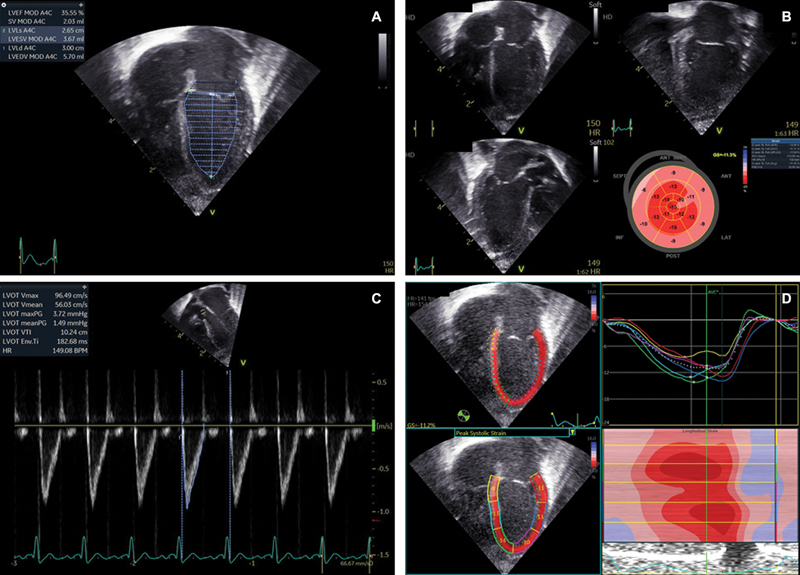

Lacosamide (Vimpat Harris FRC Corporation, 2022 UCB, Inc. Smyrna, GA 30080) is an antiseizure medication, which acts through blockage of voltage-gated neuronal sodium channels. Its recent implementation in the neonatal population has been extrapolated from adult and pediatric data suggesting a favorable safety profile. Of note, preterm infants have unique developmental characteristics that may predispose them to increased risk of adverse reactions. We present a case of a preterm neonate who developed left ventricular dysfunction coinciding with the initiation of lacosamide.